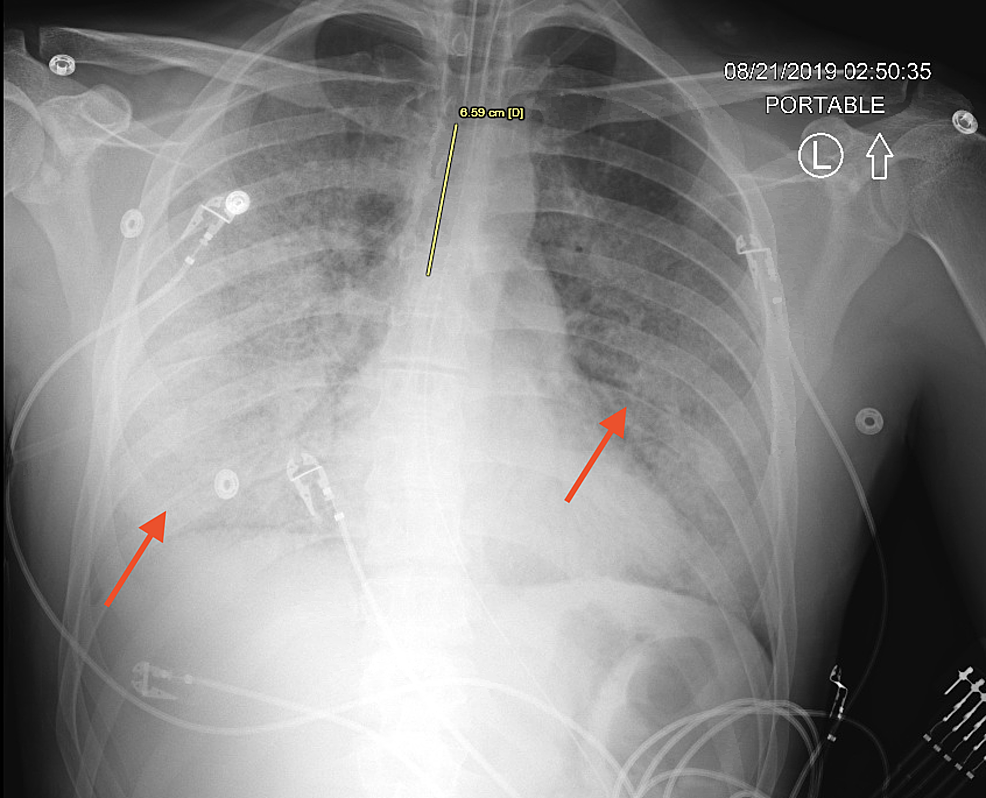

Post Intubation Chest X Ray Anteroposterior chest radiograph shows left tension pneumothorax after endotracheal intubation. Anteroposterior chest radiograph shows left tension pneumothorax after endotracheal intubation. It is common practice to obtain an immediate (stat) chest radiograph (cxr) upon completion of an endotracheal intubation to. In the operating room, it is not. In the operating room, it is not.